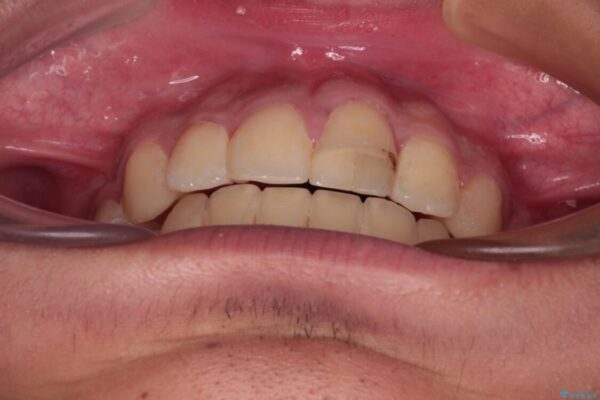

治療後

• 膨らんだ口元 ワイヤー装置での抜歯矯正 治療後画像